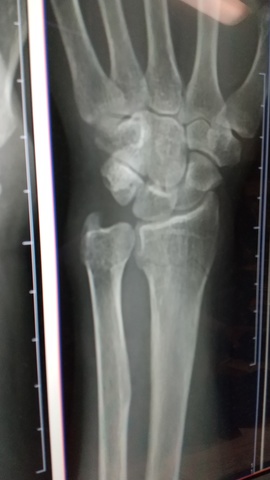

自分の不注意から撓骨遠位端骨折と尺骨のヒビで療養中です。

昨日3回目の受診でしたが尺骨も骨折でした。